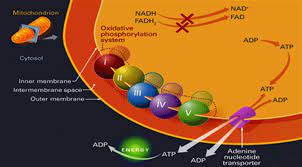

قیمت: 108٬000 تومان - دسته بندی فایل: پاورپوینتپاورپوینت فسفریلاسیون اکسیداتیو

فروش ویژه پاورپوینت حرفه ای فسفریلاسیون اکسیداتیو با تخفیف استثنایی فقط 79 هزار تومان تعداد اسلاید: 61 اسلاید